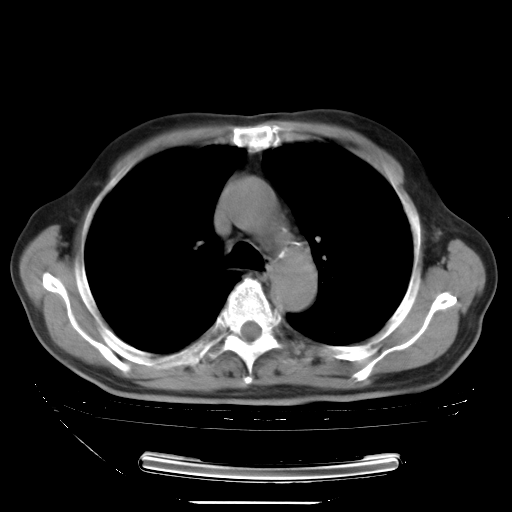

今天复查肺部CT,发现双肺广泛磨玻璃样改变。所以我把3月19日和5月9日相隔50天的肺部CT上传。请大家会诊。

2009年3月19日肺部CT片。

2009年3月19日肺部CT